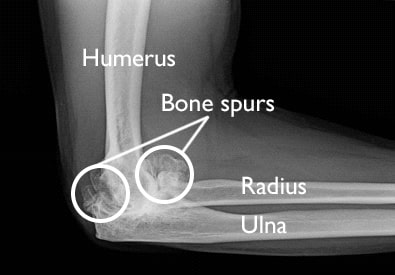

Elbow Arthritis Shoulder Elbow Orthobullets

Osteophytes do not usually cause pain but the associated arthritis might. Elbow bone spurs are common in pitchers and other throwing athletes as well as those with elbow arthritis. Ice and anti-inflammatory medications are commonly used depending on the location of the spur.